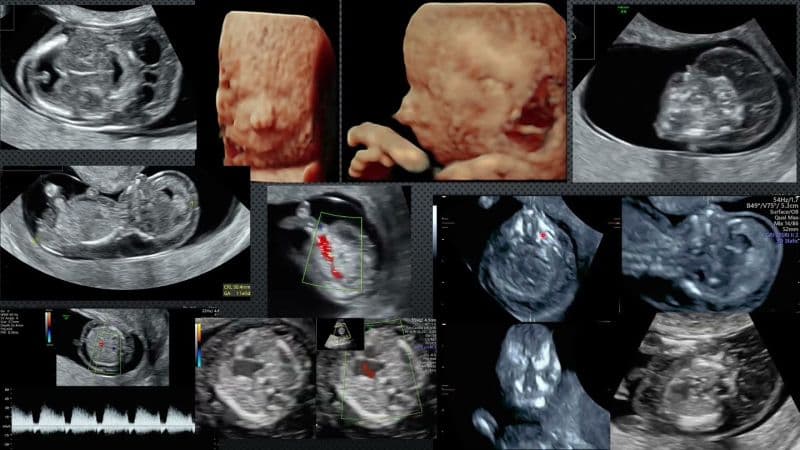

5. Phát hiện sớm và chẩn đoán các vấn đề của thai nhi trước sinh

Vì tính chất nghiêm trọng của bệnh, việc thực hiện các xét nghiệm sàng lọc sớm là vô cùng cần thiết:

- Xét nghiệm NIPT (Sàng lọc không xâm lấn): Đây là phương pháp tối ưu hiện nay, có thể thực hiện từ tuần thứ 9 của thai kỳ.Nhờ phân tích ADN tự do của thai nhi trong máu mẹ, xét nghiệm NIPT có thể sàng lọc hội chứng Edwards với độ tin cậy vượt 99%.

- Xét nghiệm chẩn đoán: Nếu kết quả sàng lọc nguy cơ cao, bác sĩ sẽ chỉ định chọc ối hoặc sinh thiết gai nhau để phân tích bộ nhiễm sắc thể (Karyotype) nhằm đưa ra kết luận cuối cùng.